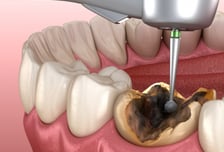

치아가 건강해야 몸도 건강하다…'이 빠진' 중년, 암 발병률 '쑥'

치아·잇몸·혀 등 구강의 건강 상태가 '전신'의 건강을 좌우할 수 있다는 연구 결과가 속속 나온다. 그간 구강 중에서도 치주염, 치아 상실에 한해 전신 건강과의 연관성이 연구됐지만, 최근엔 생존율과 암 발생률에 구강 건강이 관여한다는 새로운 연결고리가 발표돼 주목된다. 먼저, 구강질환이 암 발생률을 높인다는 사실이 국내 연구 결과로 입증됐다. 서울대병원 공공진료센터 김계형 교수와 서울시보라매병원 공공부문 이승연 박사는 2009년 구강검진을 받은 성인 384만5280명을 대상으로, 2006~2019년 국민건강보험공단 진료 기록과 통계청 사망 자료를 연계해 10년 이상 추적 관찰했다. 연구팀은 구강질환을 △충치 △치은염 △치아 상실의 세 가지로 구분해, 유무에 따라 전체 암과 부위별 암의 발생률·사망률을 분석했다. 그랬더니 전체 암 발생은 총 18만1754건으로, 구강질환이 있는 사람에서 그렇지 않은 사람보다 암이 더 많이 발생했다. 특히 치아 상실이 있는 경우 대장암은 13%, 간암은